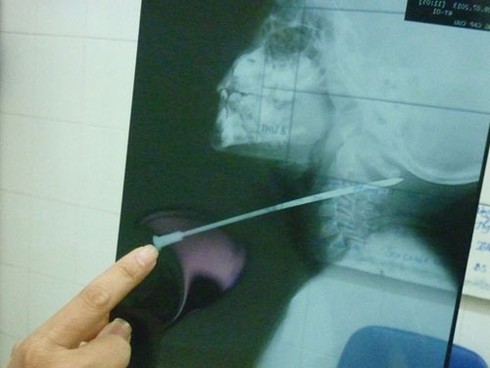

Tin từ Bệnh viện Đa khoa tỉnh Lâm Đồng ngày 10-7 cho biết: Sức khỏe của cháu Phan Hữu Nhật Duy (5 tuổi, ngụ khu phố 8, thị trấn Liên Nghĩa, huyện Đức Trọng, tỉnh Lâm Đồng) đang tiến triển tốt sau khi được phẫu thuật lấy chiếc nan hoa xe máy ra khỏi cổ.

Trước đó, sáng 9-7, khi đứng chơi trên ghế, trượt chân ngã xuống đất, Duy bị một nan hoa xe máy đã được mài nhọn đâm xuyên cổ. Các bác sĩ Bệnh viện Đa khoa Lâm Đồng phải mất 2 giờ phẫu thuật mới lấy được chiếc nan hoa ra khỏi cổ Duy.

| Chiếc nan hoa xe máy xuyên qua cổ cháu Phan Hữu Nhật Duy |